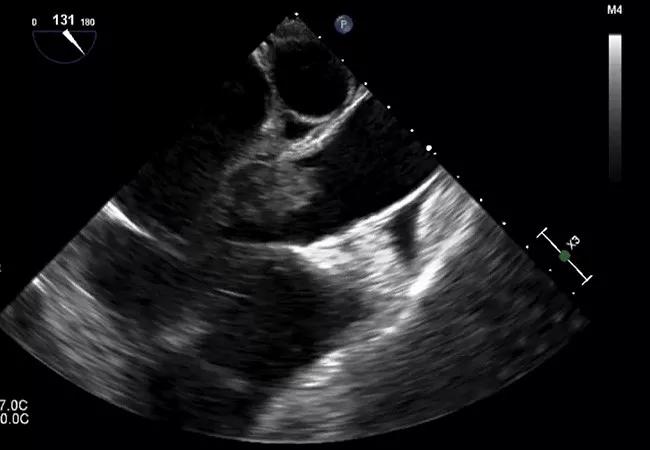

18-HRT-242_large endocarditis vegetation_450x650